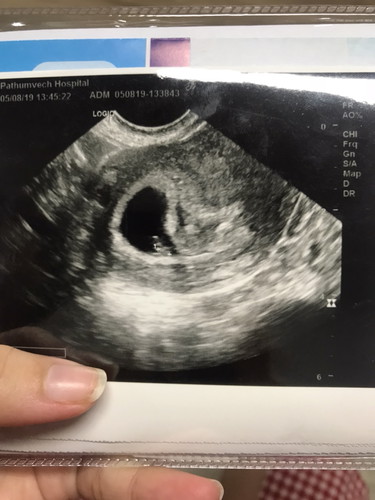

ช่วยบอกทีคะท้อง6สัปด่ห์เจอตัวนิดเดียวแต่ยังไม่เตอหัวใจเต้น

มีแม่ท่านใดท้อง6สัปดาห์ซาวเจอตัว3มิล หมอนัดตรวจอึกครั้ง19/08/62 ต้องเจอหัวใจ ไม่งั้นแปลว่าผิดปกติ เครียดมาก วิตกกังวงใจมากคะ มีแม่ท่านไหนเคยเป็นแบบนี้ ปกติไหมคะตอนนี้ รบกวนด้วยคะ เครียดมากๆๆ

ของเราซาวด์ตอน 6weeks เหมือนกันค่ะ เจอหัวใจเต้นแล้ว แต่ต้องซาวด์ทางช่องคลอดถึงเจอ เพราะตัวน้องยังเล็กมากเลยค่ะ หมอจะให้มาตรวจอีกทีเป็นเดือนเลยค่ะ เพราะมีภาวะเสี่ยงหลายๆอย่างที่สามารถเป็นไปได้ ทางที่ดี คุณแม่ทำใจสบายๆ ไม่เครียดนะคะ ขอให้ซาวด์รอบหน้าเจอน้องตัวโตๆแข็งแรงๆนะคะ

ของเราตอนไปตรวจก็เห็นตัวนิดเดียว เเต่หัวใจเต้นเเรงดี ยังไงเป็นกำลังใจให้นะคะ สู้ๆค่ะ อย่าเครียดนะคะคุณเเม่บางทีลูกอาจตัวเล็กมากเลยยังไม่ค่อยได้ยิน